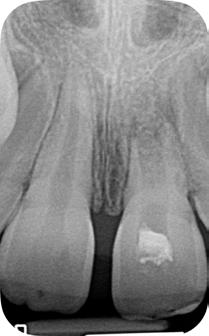

Paciente del género femenino, 44 años de edad, asistió al consultorio para realizar el retratamiento endodóntico del diente 22. Hemos hecho la radiografía inicial para evaluar el diente 22 y nos encontramos con una imagen radiolúcida en forma de globo, caracterizando una reabsorción radicular interna en el diente 21. Hemos hecho, entonces, una nueva radiografía para evaluar el diente 21 (Figura 1).

Figura 1 - Radiografia inicial

Durante la anamnesis la paciente relató haber sufrido un cabezazo del hijo hace dos años. El examen clínico reveló presencia de faceta de porcelana en el diente 21, prueba de sensibilidad pulpar positiva, ausencia de sintomatología y ausencia de alteraciones en la mucosa gingival. Solicitamos una tomografía computarizada cone beam (Figuras 2, 3 y 4) para confirmar el diagnóstico, evaluar si la reabsorción era comunicante o no y para estudiar la estructura dental radicular remanente.